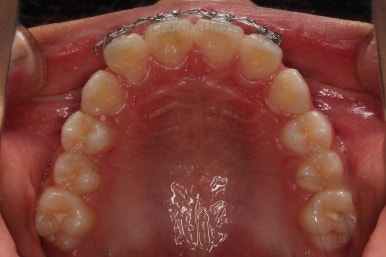

부산소아교정 초진 시 입안의 모습입니다.

윗니가 아랫니보다 많이 앞에 나와있고요.

심지어는 틈새가 벌어지기까지 했습니다.

윗니가 배열 되어있는 U자 형태(그릇 형태)가 아랫니보다 좁은 양상이고요.

이런 앵글씨 2급 부정교합에서는 아랫니가 윗니와 만나기 위해 솟구쳐서 과개교합(아래 앞니가 윗니 뒤쪽으로 깊숙히 올라가 있는 상태)이 나타나기까지 합니다.

트윈블락 장치와 더불어 윗니 앞니는 가지런하게 하기 위해서 브라켓-철사 장치가 부분적으로 들어갔는데요.

아래턱이 성장하기 위해서 너무 삐뚠 윗니 앞니는 아래턱이 앞으로 나오는 걸 방해하기 때문에 부분적으로 부착형 장치를 쓸 수 밖에 없는 상황이었습니다.

윗니에 들어가는 장치는 악궁확장 기능도 들어가 있어서 위턱을 넓히며 아래턱을 앞으로 내어주는 3차원적인 조절이 가능했습니다.